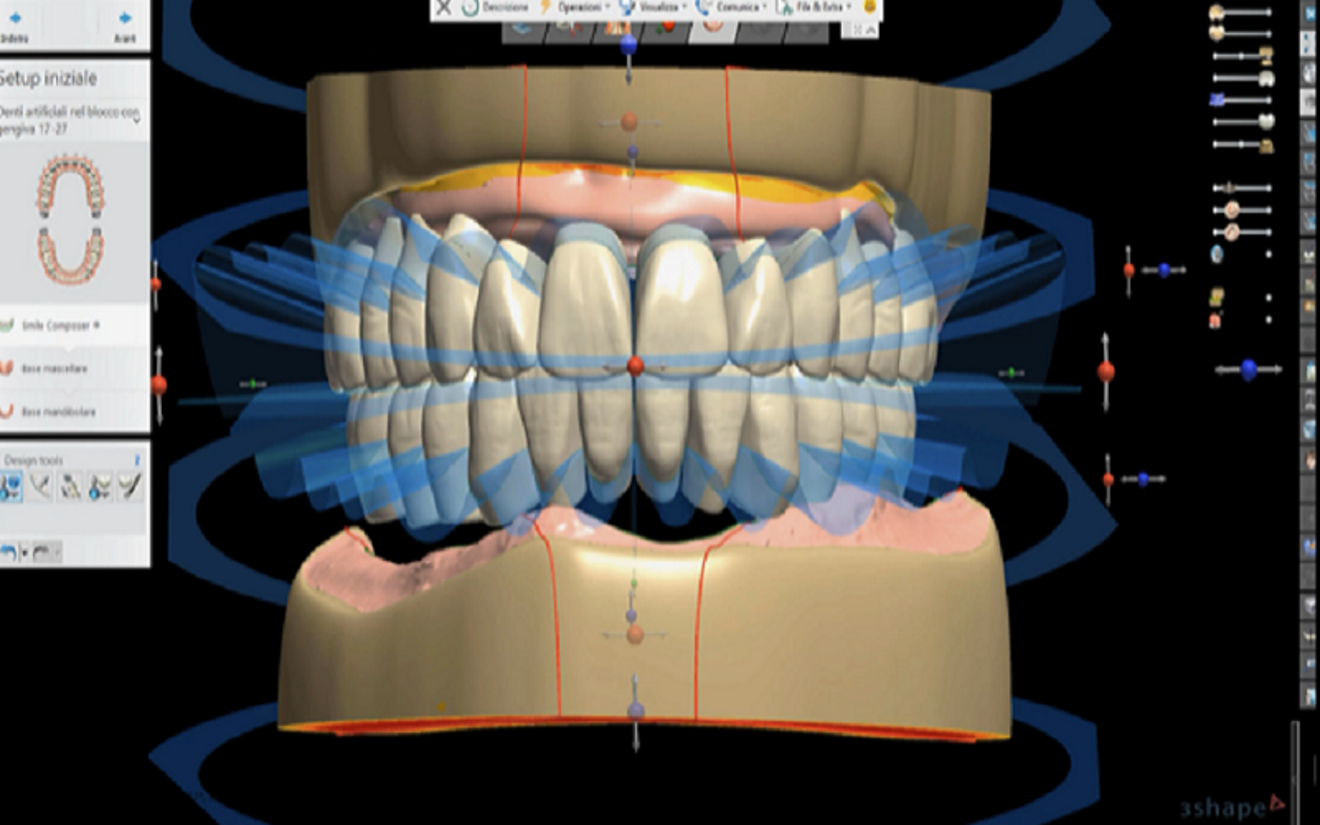

The 3D files of the prostheses were exported to the Ivotion denture system’s specific CAM module (Ivoclar; Figs. 4–6). The prostheses were milled using the Ivoclar-exclusive Shell Geometry processing capability of the R5 (Figs. 7–9). In 4 hours, the complete maxillary and mandibular prostheses had been fabricated (Fig. 10). For the maxillary prosthesis, we immediately relined it after removing the framework that had been screwed to the prosthesis and then screwed it in (Fig. 11). Re-evaluation with a digital facebow and data comparison were made possible by remote control (Figs. 12 & 13).

Fig. 6: Maxillary and mandibular prostheses designed with Ivotion libraries.